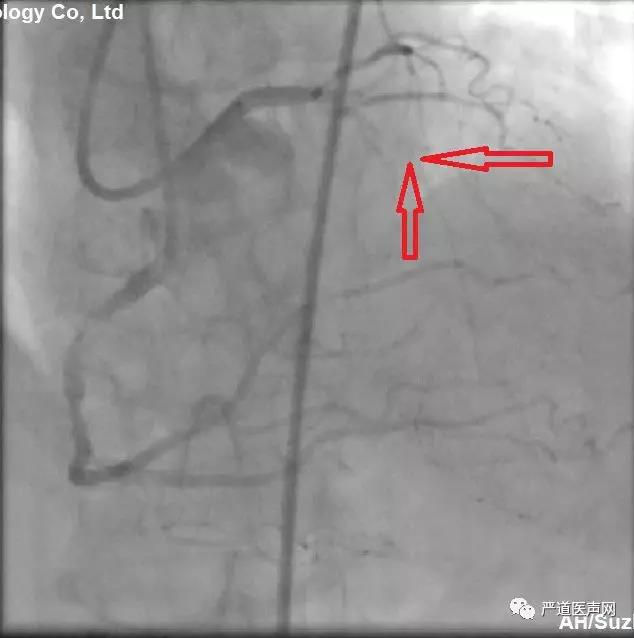

尽管闭塞LAD入口不清,从蜘蛛位和肝位造影很难确定CTO入口位置,但仔细分析造影看,仍可发现,最为可能的入口为下图中两处箭头的一处。

从头位及右肩位,提示LAD走形,隐约看到对角支前降支走向。闭塞段不长,基本符合我们术前预判的第一种情况。如果造影提供信息有限,应尽可能优先使用IVUS指引下寻找入口。